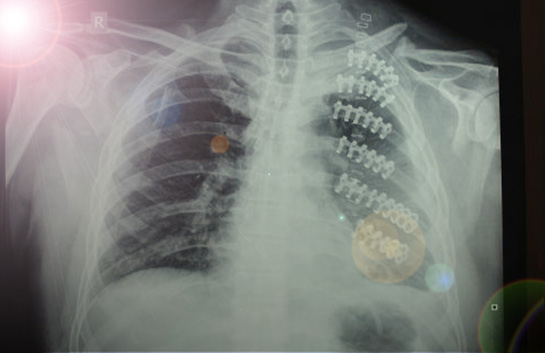

Tanı Yöntemleri Kaburga çatlağının tanısı, genellikle fizik muayene ve görüntüleme yöntemleri ile konulur. Fizik muayene sırasında doktor, ağrılı bölgeyi kontrol eder ve derin nefes alma sırasında ağrının artıp artmadığını değerlendirir. Görüntüleme yöntemleri arasında: